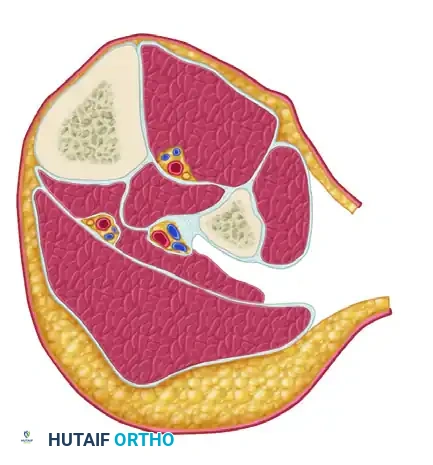

FASCIOTOMY FOR ACUTE COMPARTMENT SYNDROME OF THE THIGH

The thigh is anatomically divided into three distinct compartments: anterior, posterior, and medial. Because the thigh compartments possess a larger volume and greater compliance than those of the leg, thigh compartment syndrome is relatively rare. However, when it occurs, it is typically the result of massive blunt trauma, femur fractures, or prolonged compression.

FASCIOTOMY FOR ACUTE COMPARTMENT SYNDROME OF THE LEG

The lower leg is the most common anatomical site for acute compartment syndrome. It consists of four rigid compartments: Anterior, Lateral, Superficial Posterior, and Deep Posterior.